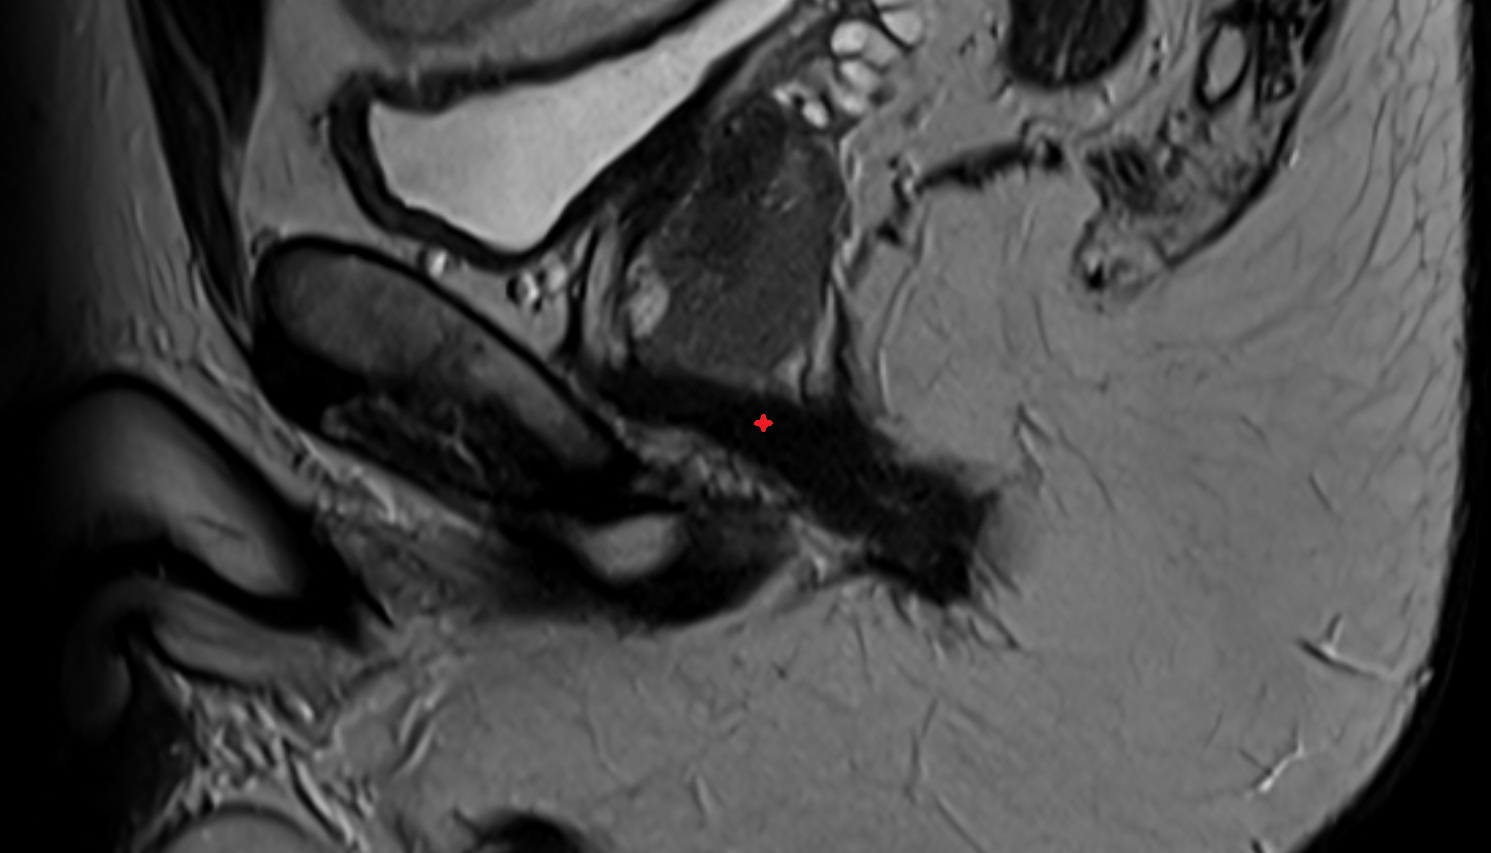

- Peripheral zone of prostate

- Central zone of prostate

- Transitional zone of prostate

- Cervix of uterus

- Endocervical canal

- Stroma of the cervix

- Internal os of the cervix

- External os of the cervix